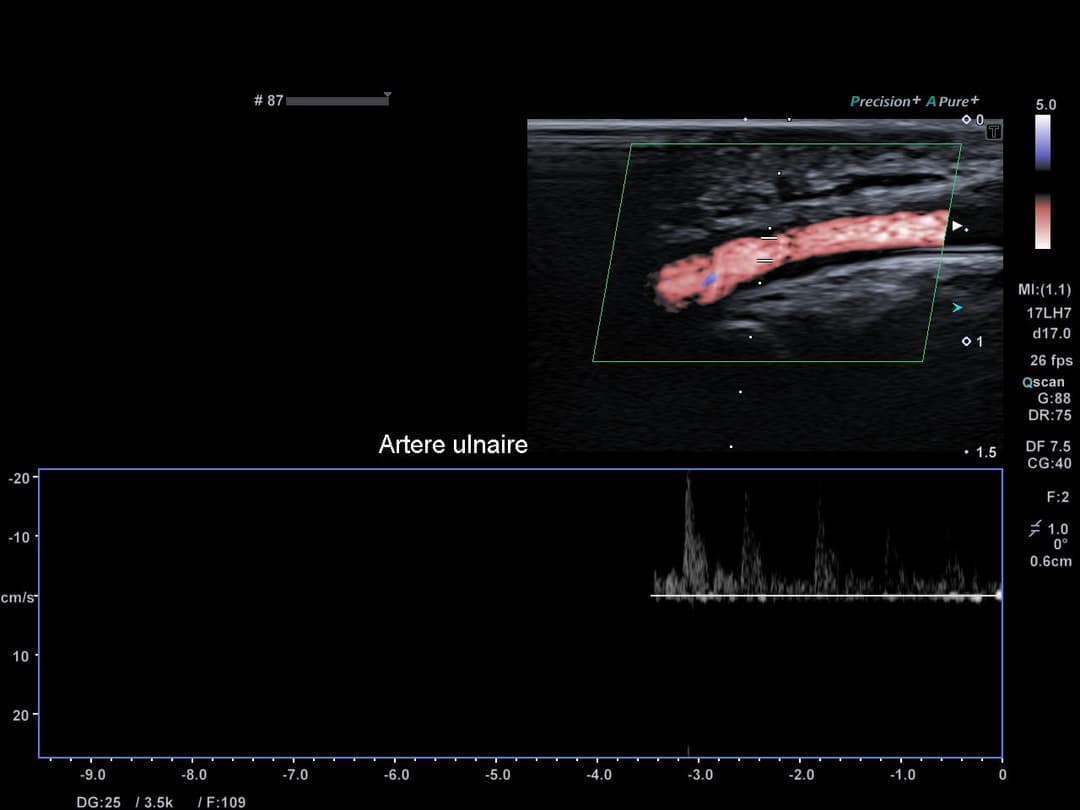

Bonne perméabilité de l'artère ulnaire